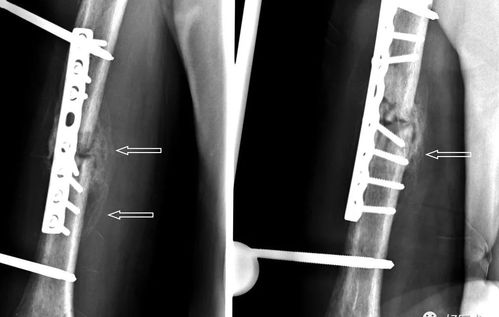

术后5周骨折处可见骨痂形成

术后3周骨折对位良好,大量骨痂生长.

【影像表现】可见骨痂形成,但仍可见骨折线.